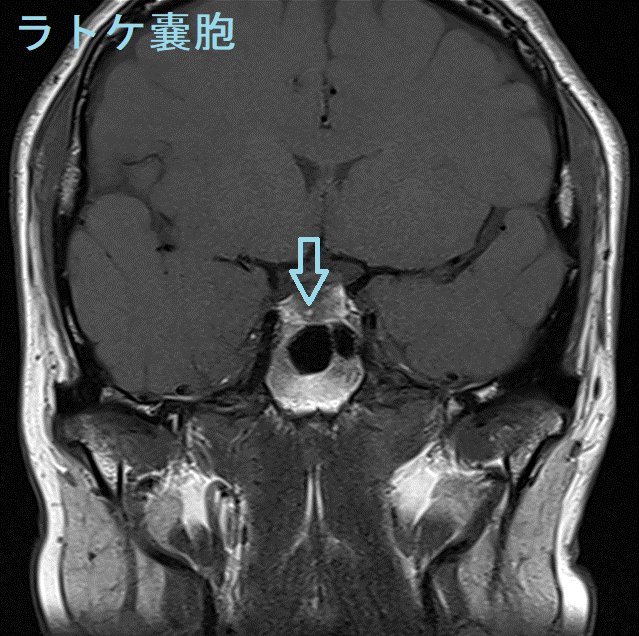

ラトケ嚢胞(ラトケのう胞)とは胎児期の袋が消えずに残ったものです。

- ラトケ嚢胞(ラトケのう胞)内の粘液が増えると、大きくなったラトケ嚢胞(ラトケのう胞)が下垂体や視神経を圧迫して、下垂体機能低下症・頭痛・視力障害をおこします。

MRI検査では

- T1強調;50% 高信号(蛋白成分が多い)、50% 低信号

- T2強調;70% 高信号、30% 等-低信号

- T1+ Gd造影剤;造影効果なし、周囲辺縁のみ造影される